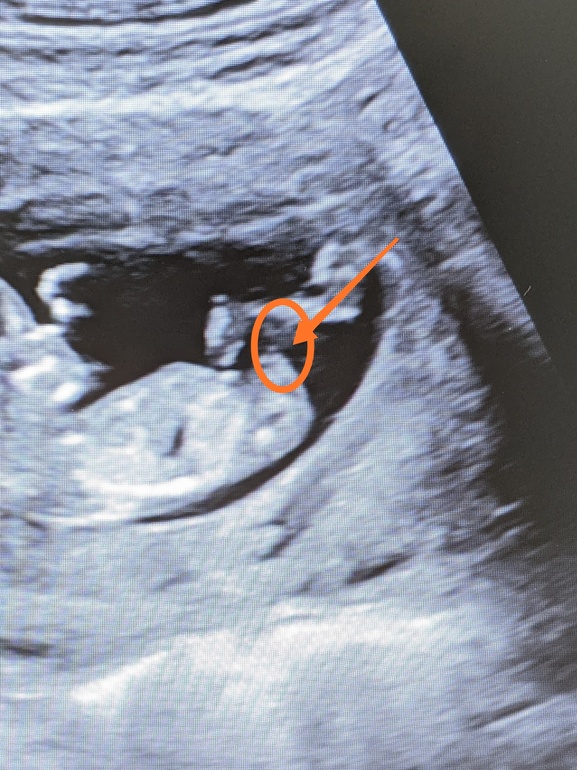

Узи 12 недель. Определить пол.

Вопросы про УЗИ, обследования и анализы: что, где, как, когда?Мне кажется или я вижу девчачью фасолинку? Кто-то еще видит, или мерещится уже?)

Нет, это мальчик определённо. Половой бугорок у девочек параллельно позвоночнику а у вас ого го как не параллельно 😁